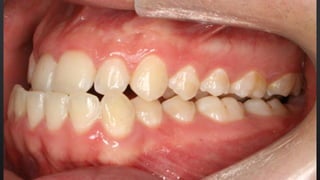

• OVERJET OU SOBRESALIÊNCIA

RELAÇÃO ENTRE ARCOS

TRESPASSE HORIZONTAL

• REFERE-SE AO DISTANCIAMENTO ENTRE OS INCISIVOS SUPERIORES E INFERIORES

• NORMALMENTE 2MM

• OVERJET OUSOBRESALIÊNCIA RELAÇÃO ENTRE ARCOS TRESPASSE HORIZONTAL • REFERE-SE AO DISTANCIAMENTO ENTRE OS INCISIVOS SUPERIORES E INFERIORES • NORMALMENTE 2MM